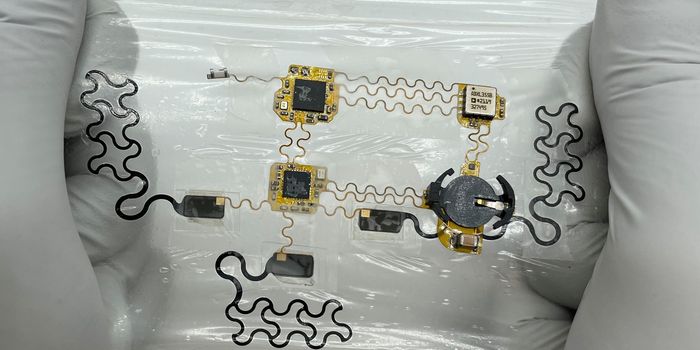

MAR 13, 2024Clinical & Molecular DXAfter gastrointestinal surgeries, patients are at serious risk of complications. But a cutting-edge device from Northwes ...

-